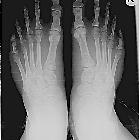

This is a

digital x-ray photograph of Cjottawa"s feet, which exhibit the condition "Morton"s Toe." It will be used on the Wikipedia page: https://en.wikipedia.org/wiki/Morton"s_toe

rechter Fuß. Der Fußtyp mit geradem Abschluss aller Zehen auf einer Linie wird als "Römischer Typ" bezeichnet.

Römischer

Fußtyp: Die Endglieder aller Zehen schließen praktisch auf einer Linie ab, die Zehen sind gleich lang.